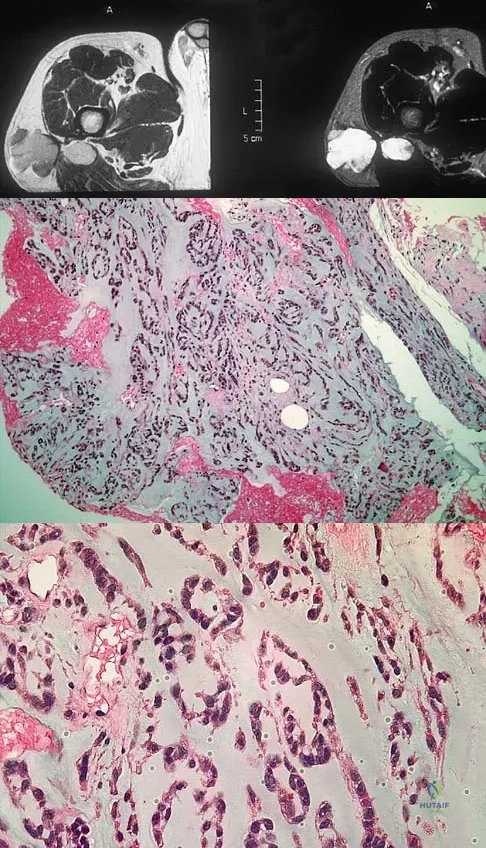

A 13-year-old boy has had a painless mass in the arm for the past 2 months. An MRI scan and biopsy specimens are shown in Figures 46a through 46c. What is the most likely diagnosis?

Explanation

A 14-year-old boy has an asymptomatic mass on the right arm. MRI scans and biopsy specimens are shown in Figures 51a through 51d. Immunostaining is positive for desmin. Additional staging studies should include

Explanation